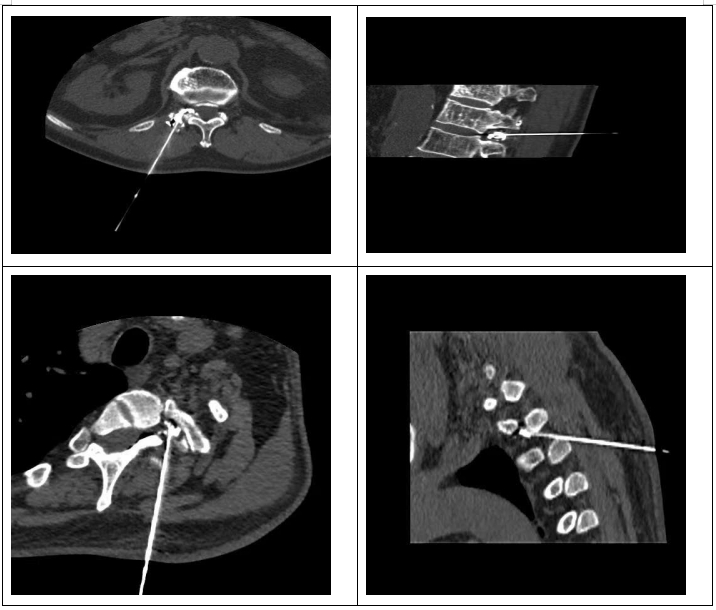

精准微创技术,直击疼痛根源。面对两位患者的病情,我院麻醉疼痛科、康复科、放射科迅速展开会诊,经详细评估后,决定采用CT引导下脊神经根脉冲射频调节联合神经根阻滞术为其治疗。放射科蒲鹏主任医师、泽旺初技师团队基于128排螺旋螺旋CT搭载的高分辨率动态三维成像技术,凭借毫米级精度构建穿刺通道三维模型,实现病灶靶区的立体导航定位规划最优穿刺路径,为临床制定个体化精准诊疗方案提供可视化决策支持,就像给医生装上了“透视眼”,确保治疗操作准确无误。在此基础上,通过脉冲射频调节,可有效调节神经功能,降低神经的敏感性;神经根阻滞术则能直接阻断疼痛信号的传导,双管齐下,从根源上解决疼痛问题。

整个手术过程在麻醉疼痛团队侯静主治医师、历叶林副主任医师、夏雷医师以及康复科李晓医师的配合下仅耗时1小时左右,创口微小,对患者身体的损伤极小。术后,两位患者疼痛症状便得到了明显缓解,脸上也终于露出了久违的笑容。